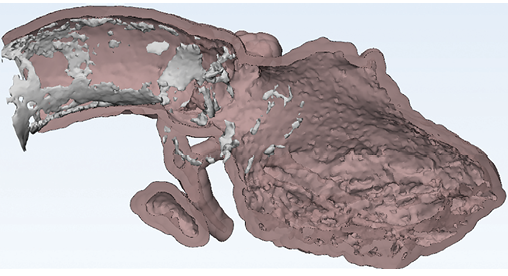

Accessing data from the scanner to create high-quality 3D models is not always practical, since source data at most institutions is routinely purged to save space. Also, the source data may not be accessible because images were acquired at another institution. Clinicians who use advanced 3D printing and visualization often face this problem.

“In such cases, an approach starting with already reconstructed images is really the only option to potentially avoid additional radiation exposure to the patient and boost the quality of 3D models and visualizations,” said Leonid Chepelev, MD, PhD, a radiology resident at the University of Ottawa in Ottawa, Canada.

Dr. Chepelev, a member of RSNA’s 3D Printing Special Interest Group, is exploring how AI can improve the burgeoning technology of 3D modeling. The segmentation process used in building a model can take hours and is limited by the quality of the image. AI can significantly speed up this process while improving the image quality, which is an important consideration for surgeons who might be planning, for example, to remove a tumor that is near vital structures like blood vessels. “I think all these tools will ultimately improve the accessibility of the pathology depicted by radiology and will help us to communicate with surgeons and the patient as well,” Dr. Chepelev said.